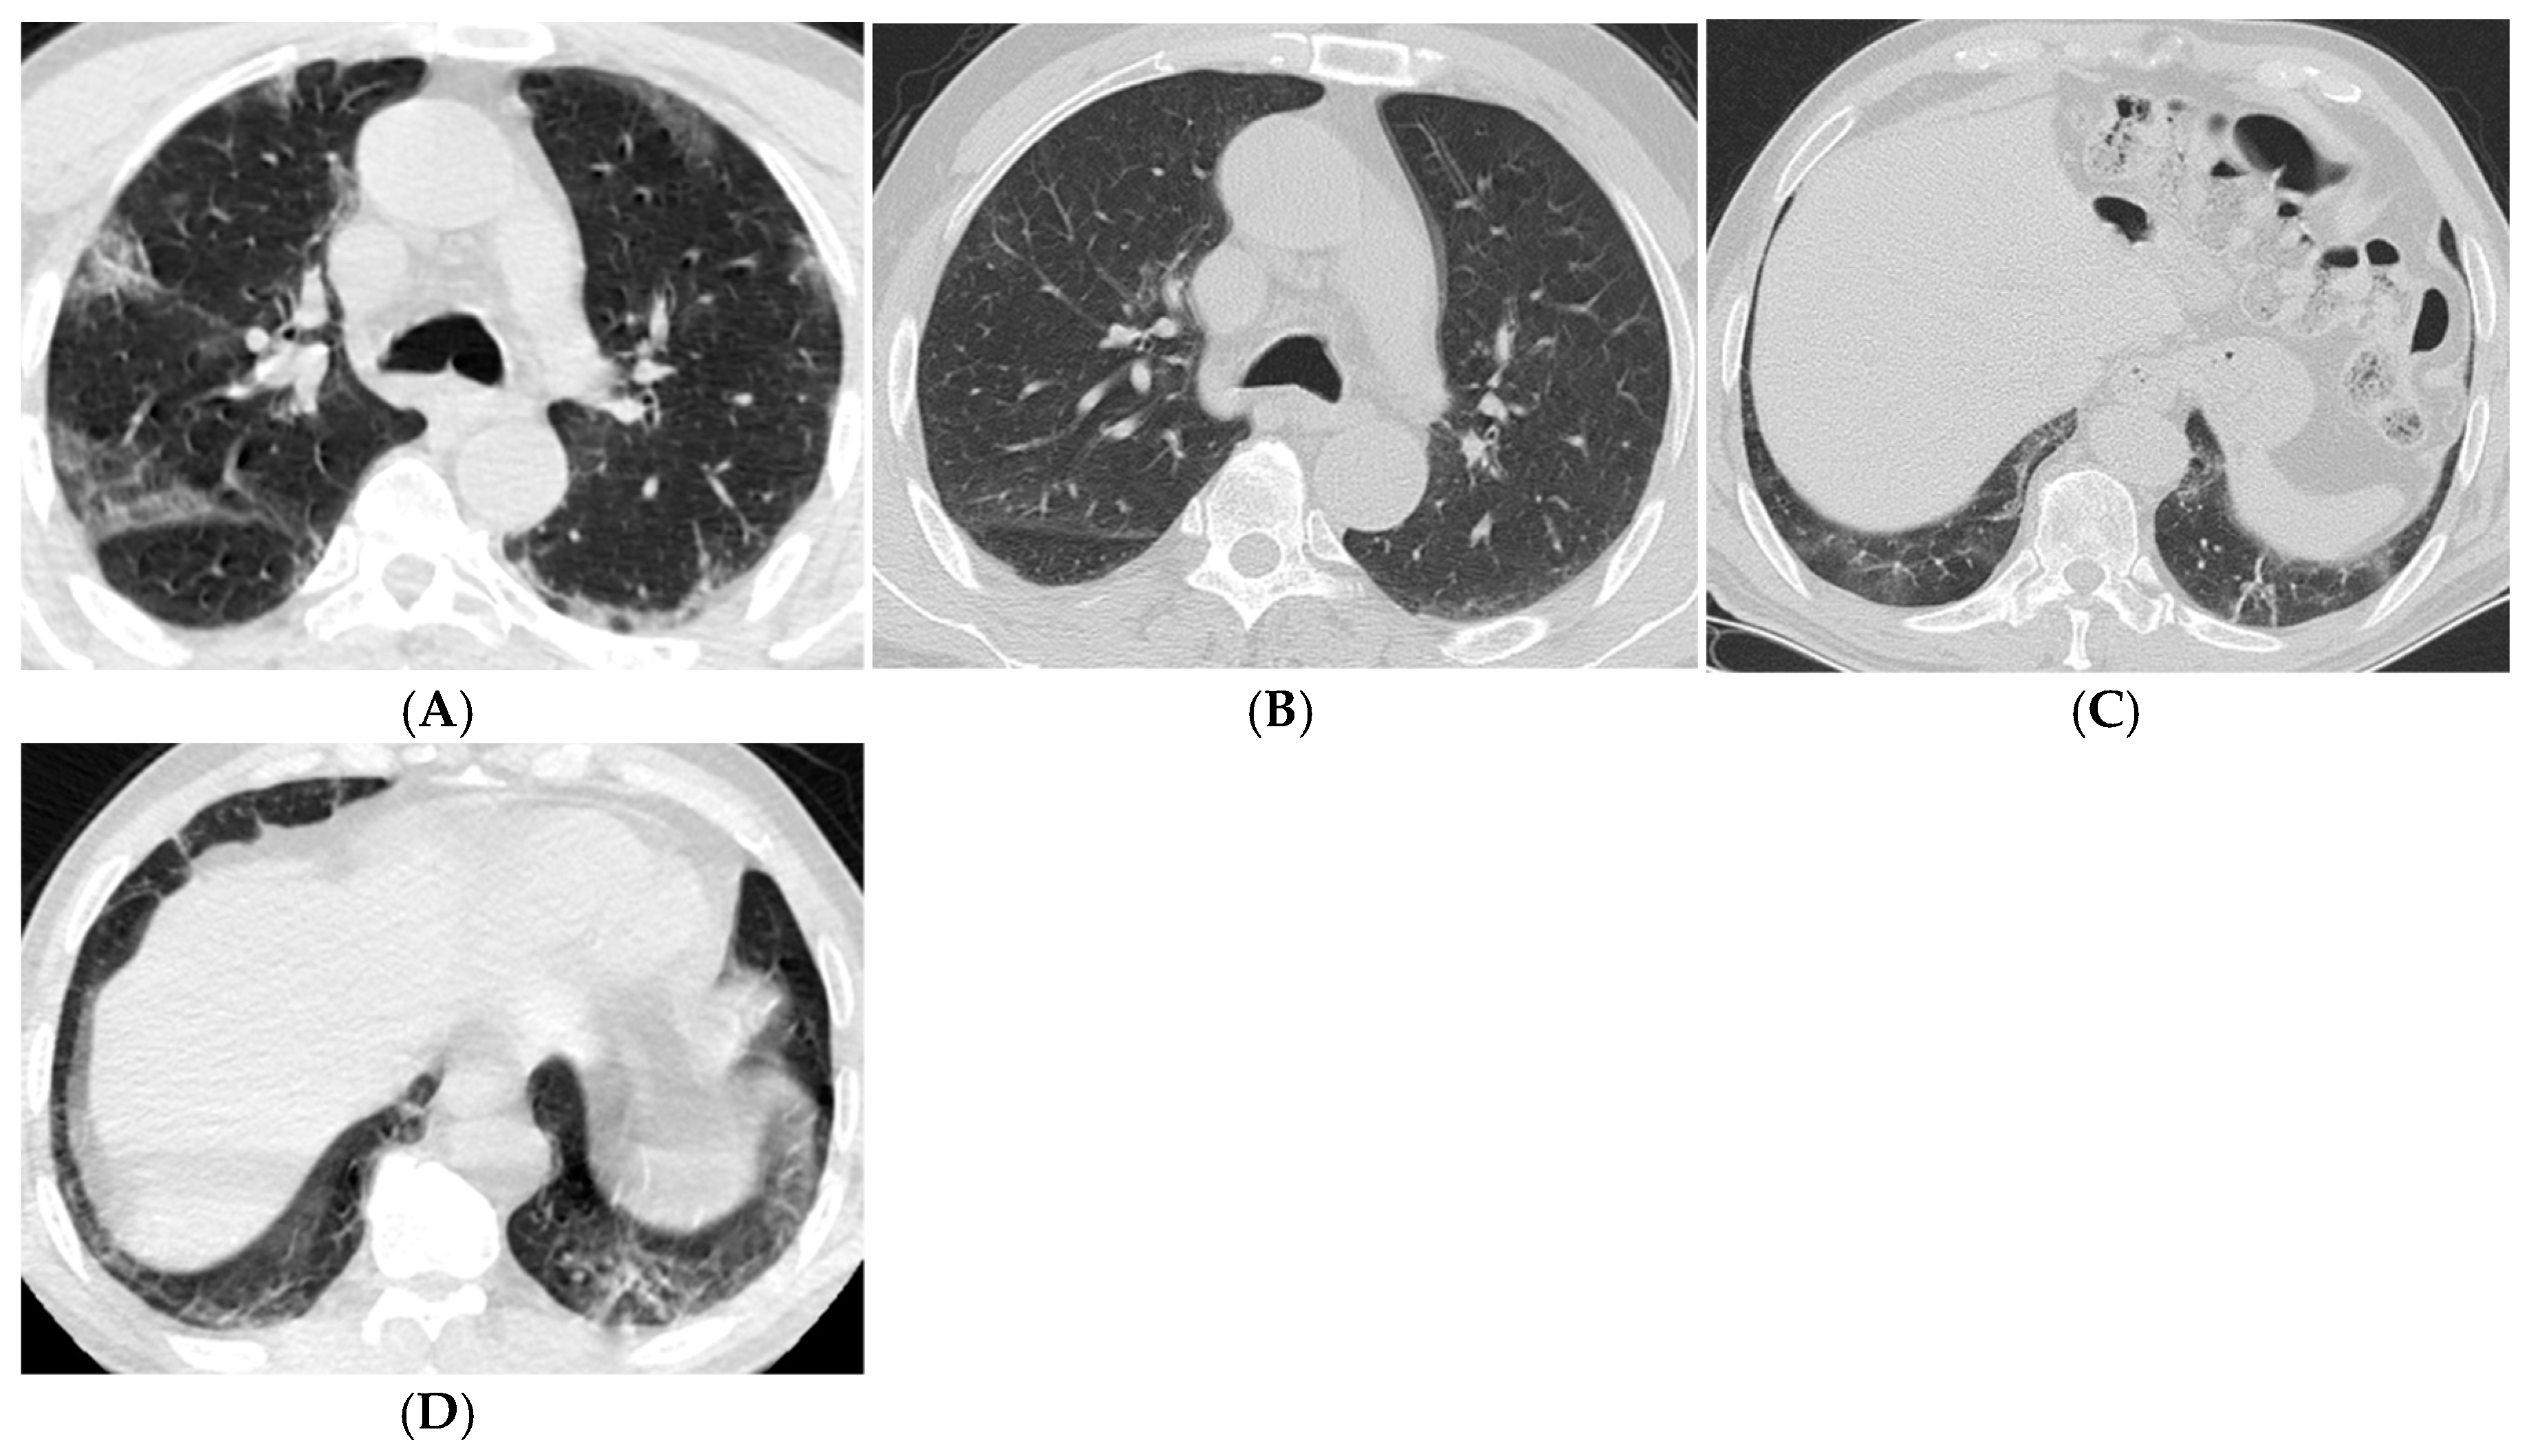

| Imaging Findings (6–12 Months) | Common Findings | Parenchymal bands, traction bronchiectasis |